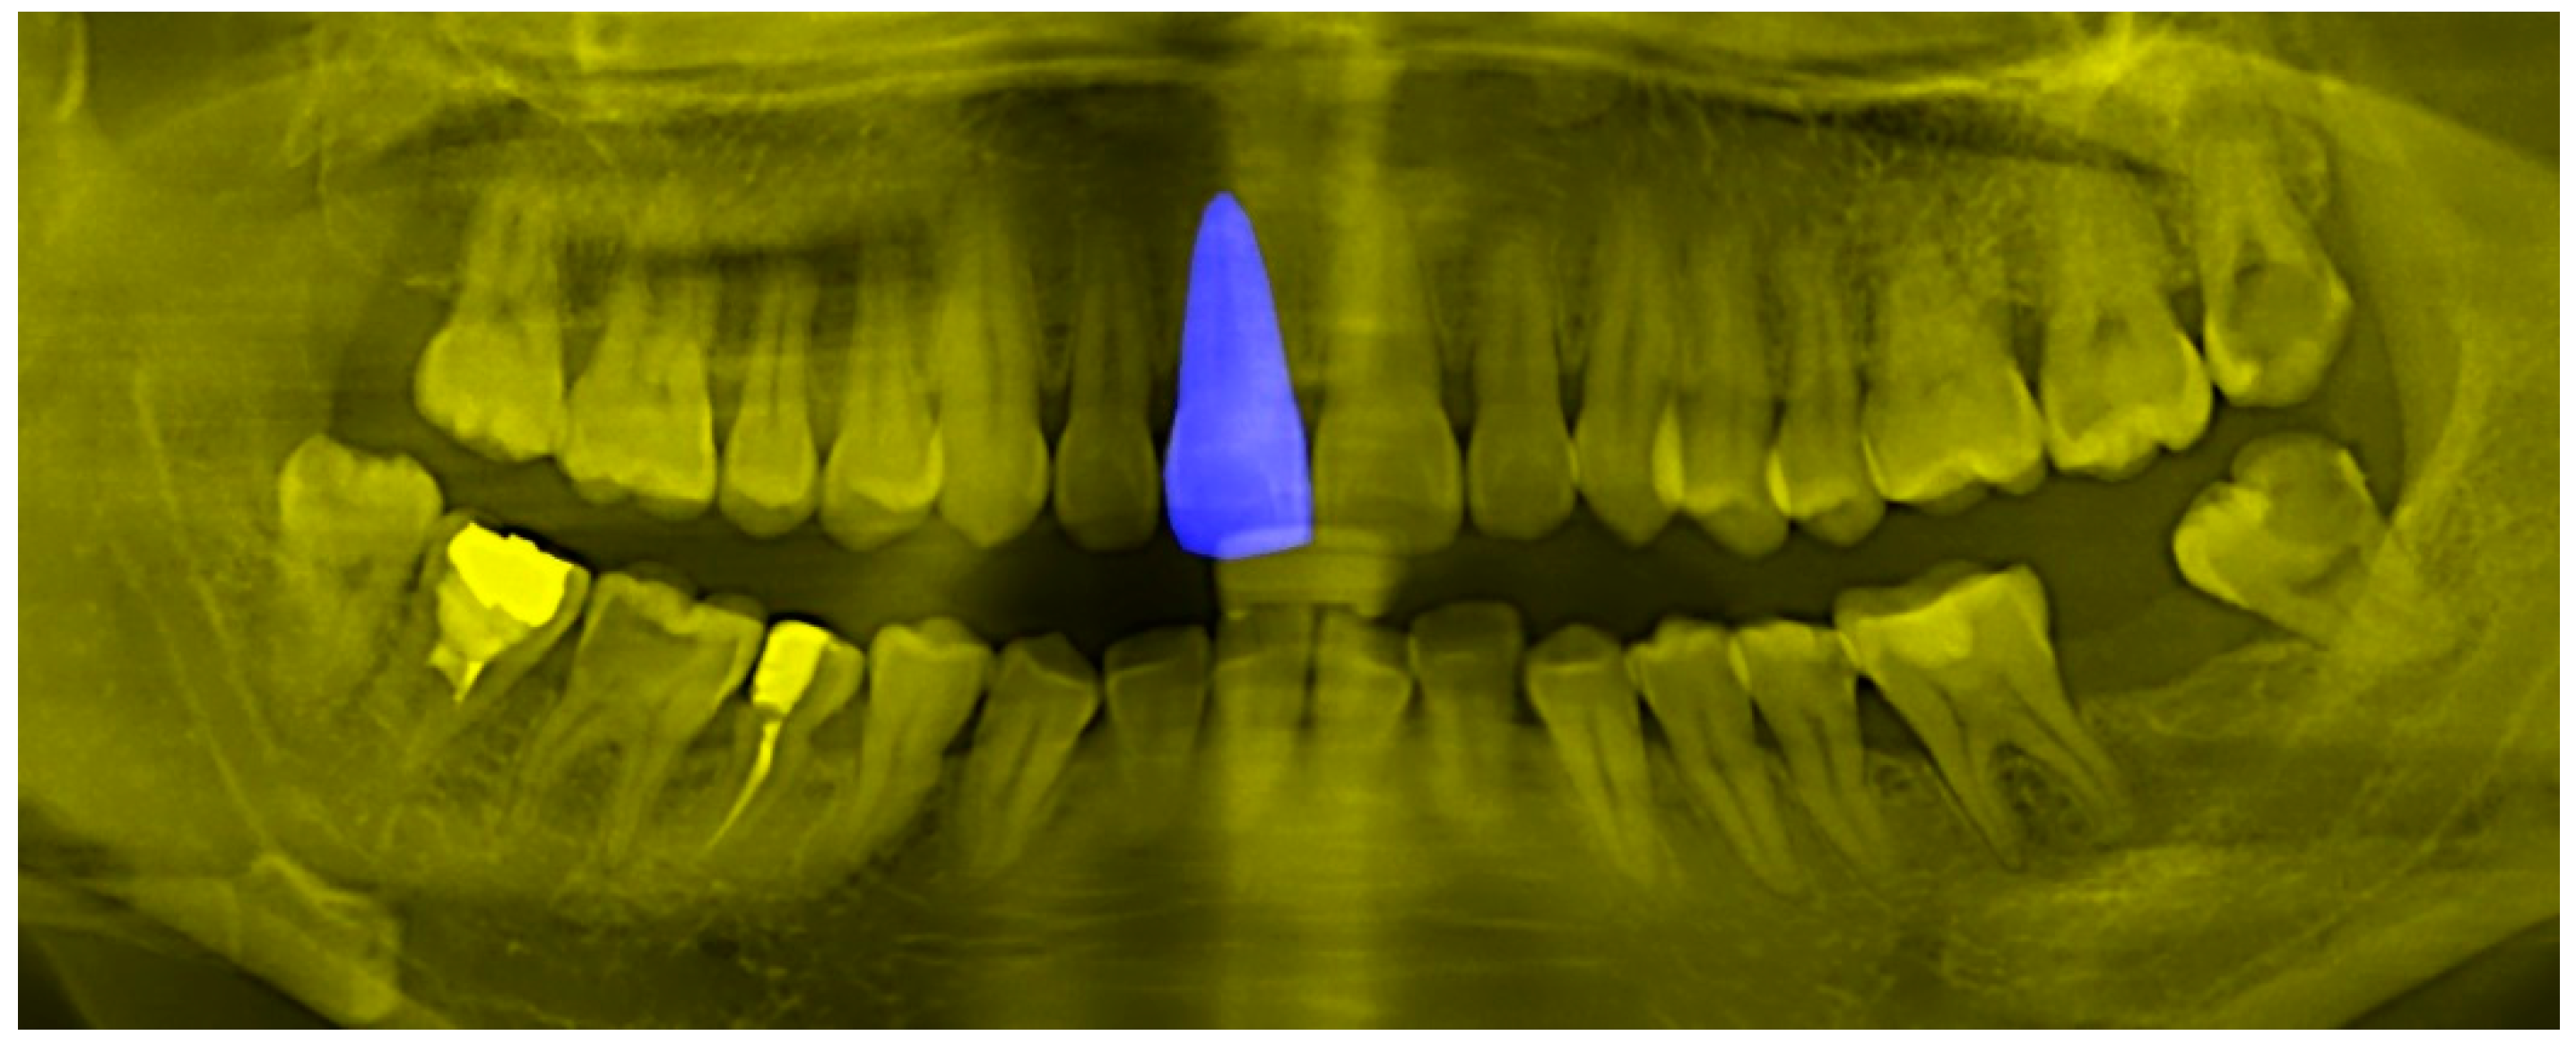

If the original sample of the tooth image is directly put into the model for training, it will lead to a poor generalization ability of the model, owing to imbalance of the black and white pixel ratio. Figure 2 shows the performance of the trained semantic segmentation model for few-shot. It can be observed that, in addition to the segmentation ability of the teeth region, there will be some incorrect segmentation regions in the area around the teeth. In order to obtain better results for dental object detection, we need to extract the key areas of the teeth from the panoramic X-ray image of the teeth, so that the ratio of black and white pixels of the image mask will be more reasonable and exclude those areas that do not need to be identified; i.e., key areas need to be framed and cut out. The model used to extract the semantic segmentation image of teeth in this paper is U-Net, and the U-Net network structure is shown in Figure 3, which performs well in small-size datasets.

Figure 2.

Key region extraction of teeth.